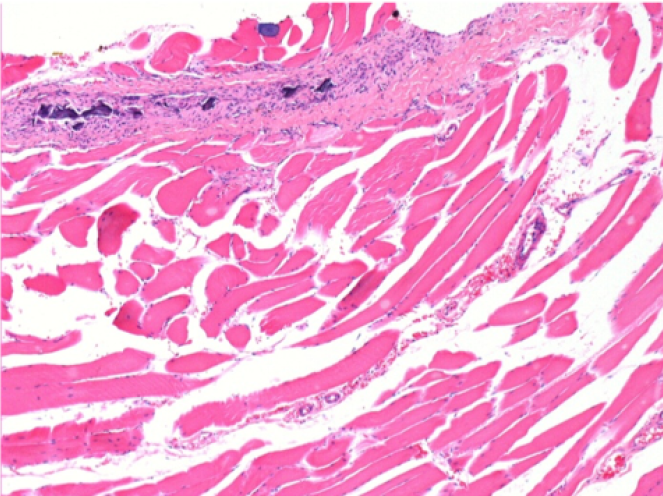

7 meses después de la inyección de Endopeel

7 meses (D210) después de la inyección IM de Endopeel 0,1 ml en el músculo pretibial derecho.

Restitutio ad integrum (restauración a la condición original) completa después de 7 meses

L : Control-100xD210

R:100xD210

L :Control 50xD210

R50X-D210